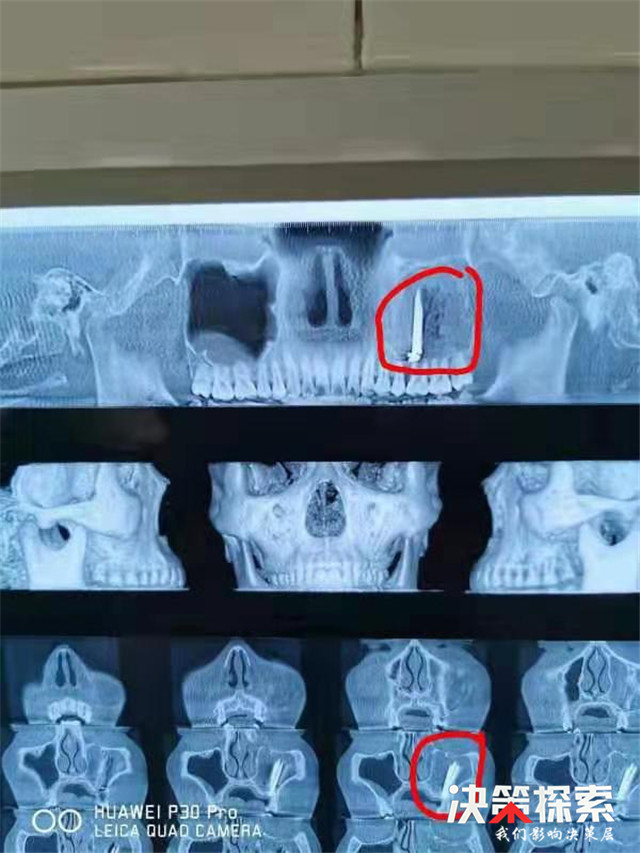

该院口腔颌面外科主任蒋子超通过口腔CT检查发现患者左侧上颌窦“钉样”高密度影,上颌窦窦腔密度增高。口腔检查发现患者左上后牙腭侧有一“莲子”般大的红色斑块。医生诊断的结果是:上颌窦异物、上颌窦炎、腭部肿物等。

“必须马上手术,以免上颌窦异物继续刺激,引起长期头痛、鼻塞流涕等影响工作和生活。”蒋子超说。和患者家属充分沟通后,医生于近日为患者实施了上颌窦异物取出术、根治术和上颌窦瘘修补术等系列手术。通过2个小时手术,医生终于从患者上颌窦内成功取出3根长约4cm的金属钉和2根长约4cm的牙签棍儿及1片瓜子皮。